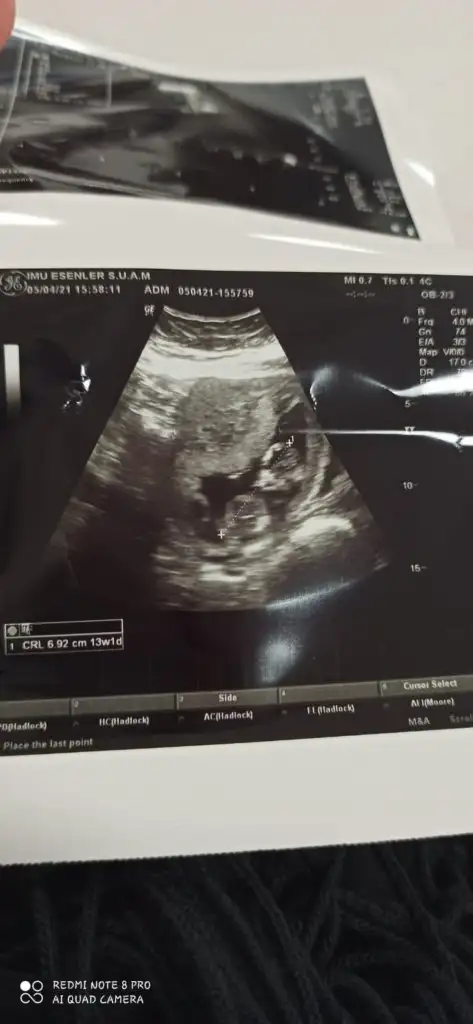

Kız görünüyorIkra meyra 16 haftalık bacak altından sence hangisine yatkın

Kız görünüyor